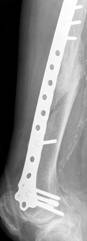

A 23-year-old man with no background history sustained a transverse fracture (Fig. 1.a) of the right tibia and fibula (AO 42 A3) after receiving a kick on the shin while playing Gaelic football. The fracture was stabilised with a 4.5mm Narrow LCP (Fig. 1.b&c) with 10-Combi holes using 6 looked screws (two screws at either end of the plate and two screws adjacent to the two middle holes over the fracture site).

Six months later on follow-up radiography there was no visible callus formation at the fracture site. At this stage he underwent removal of the two inner-most screws. Radiography six months after the 2nd procedure revealed that the fracture had healed with marked callus formation (Fig. 1.d).

Fig 1. Clinical case of a tibial fracture stabilised with a 4.5mm LCP in a 23 years old patient. The preoperative (a), post operative (b&c) and follow-up radiographs six months post removal of the two inner-most screws (d) are shown.